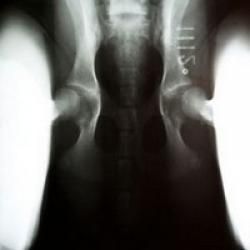

Hunden bedøves let, lægges på ryggen med benene strakt helt ud, og der tages et røntgenbillede af dens hofteled i denne position.

Hunden bedøves let, og der tages i alt 3 billeder af dens hofteled:

Et standard HD-billede som ovenfor beskrevet, et kompressions-billede hvor hofteleddet trykkes sammen, samt et distraktions-billede, hvor hofteleddet udsættes for et let press.